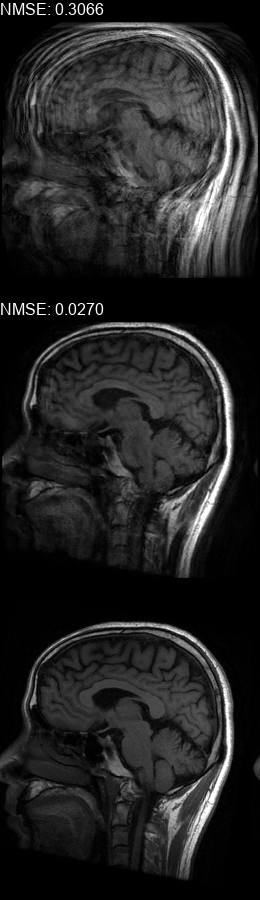

Results  Experimental results using the two presented datasets, for the fully-sampled and under-sampled k𝑘k-space scan orders, are shown in Table 1. The table presents the Normalized Mean Square Error (NMSE) obtained for each of the scan orders. For the Transaxial dataset, we only show the results for the challenging task where the DP contains only up to 707070 columns of k𝑘k-space data. All methods are able to reduce the NMSE of the corrupted scans, however the methods that incorporate the DC layer achieve a much better result. These results match our subjective visual impression of the motion-corrected images, as may be seen in Fig. 3 for simulated motion in a fully-sampled k𝑘k-space data, and Fig. 4 for an under-sampled k𝑘k-space data.

Figure 4: Motion corrected images from the Diverse dataset calculated using the 𝒰𝒮260𝒰subscript𝒮260\mathcal{US}_{260} scan order presented in Fig. 1c. The bottom row shows the fully-sampled motion-free images. The top row shows the under-sampled motion-corrupted images used as input to the correction method, these images show an additional aliasing artefacts in comparison to the ones in the top row of Fig. 3 since they are missing approximately half of the k𝑘k-space data. The middle row shows the corrected images calculated using our method. (a) contains two motions at t1=79subscript𝑡179t_{1}\!=\!79, t2=132subscript𝑡2132t_{2}\!=\!132, (b) contains a motion at t1=61subscript𝑡161t_{1}\!=\!61, (c) contains a motion at t1=83subscript𝑡183t_{1}\!=\!83, (d) contains two motions at t1=78subscript𝑡178t_{1}\!=\!78, t2=123subscript𝑡2123t_{2}\!=\!123, (e) contains three motions at t1=13subscript𝑡113t_{1}\!=\!13, t2=97subscript𝑡297t_{2}\!=\!97, t3=127subscript𝑡3127t_{3}\!=\!127, (f) contains two motions at t1=55subscript𝑡155t_{1}\!=\!55, t2=128subscript𝑡2128t_{2}\!=\!128.